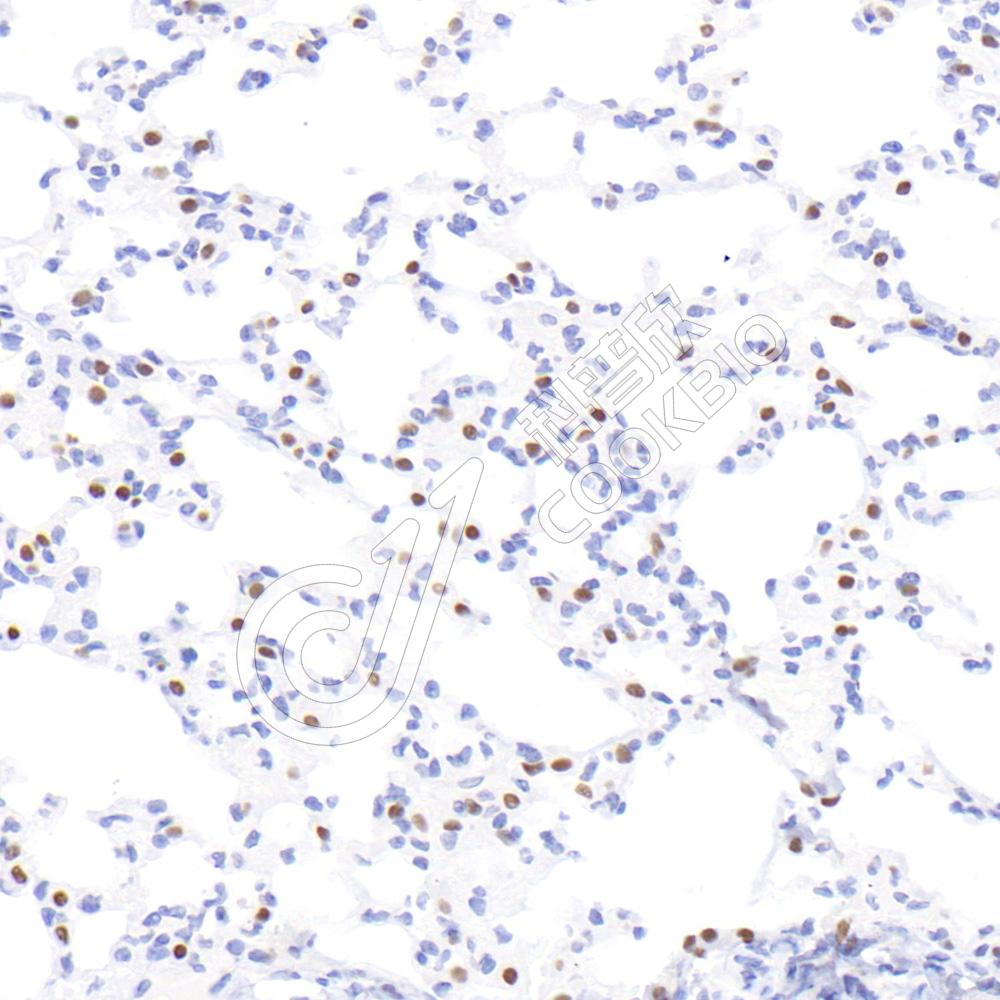

IHC检测TTF1(Thyroid transcription factor 1)蛋白(货号 K2366504).

样品: 小鼠肺, 4%多聚甲醛 (货号KSG1101) 固定12-24小时.

抗原修复: 柠檬酸抗原修复液(干粉, pH 6.0) (KSG1201), 高压锅均匀喷气计时2分钟.

—抗: 1: 800稀释, 4℃ 孵育过夜.

二抗: S-vision免疫组化多聚二抗(山羊抗小鼠), 即用型(货号KB3903), 室温孵育20分钟.